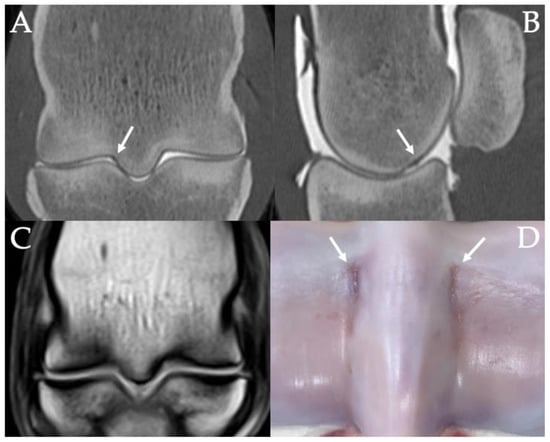

3.4. PSG Subchondral Bone Defects

3.5. PSG Cartilage Defects